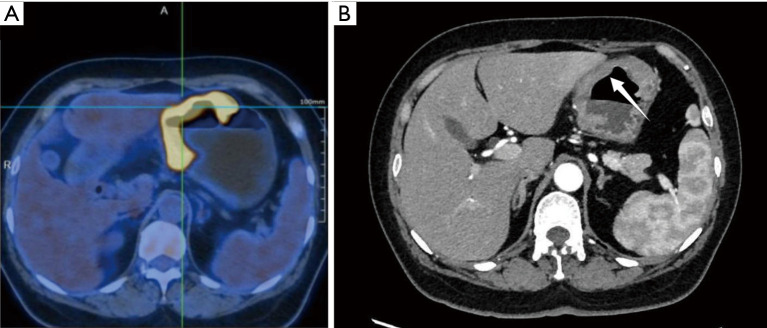

Case description: A 60-year-old female was admitted with discomfort in the upper abdomen accompanied by melena and a 6-year history of ovarian and endometrial cancer. Gastroscopy revealed a giant ulcer located in the gastric body, and biopsy pathology indicated a reproductive system origin. Subsequent 18F-fluorodeoxyglucose positron emission tomography/computed tomography (18F-FDG PET/CT) revealed a hypermetabolic lesion within the gastric wall on the lesser curvature [standardized uptake value (SUV): 23.23]. Final pathology following total gastrectomy confirmed the presence of an isolated gastric metastasis tumor originating from primary endometrial endometrioid carcinoma. The patient was discharged 11 days postsurgery and exhibited no signs of recurrence or metastasis during a 3-month postoperative follow-up.